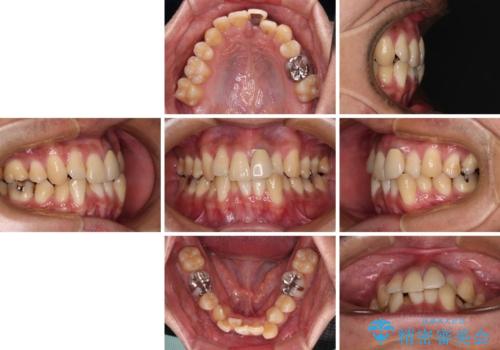

- 下顎の八重歯を気にして来院された患者様です。

左下以外、3本の第一小臼歯が既に抜去されており、左下は八重歯になっている状態でした。

左下の八重歯は手前に傾斜していたため、インビザラインによる抜歯矯正が可能と判断し、後方にある第一小臼歯を抜歯してインビザラインにて矯正治療を行うこととしました。